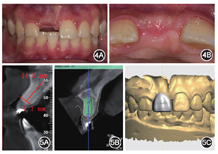

像;D:腭侧术区2周后复查愈合良好位点保存术后6个月复查,锥形束CT示骨量充足,根尖区低密度影已消失;口内见11唇侧牙龈曲线初步成形(图4)。选择窄颈种植体(ITI Straumann BL 3.3 mm×12.0 mm,士卓曼,瑞士)以最大限度减少种植体占位,余留更多成骨空间。设计唇侧保留3.0 mm,腭侧保留1.0 mm骨板厚度,植入深度位于唇侧骨缘下1.0 mm,中央螺丝从舌侧穿出的牙支持式全程种植导板(图5)。

像示11唇侧牙龈曲线初步成形;B:

面像可见卵圆窝初步成形

面像可见卵圆窝初步成形全程种植导板引导下行11牙位定点,逐级备洞,植入窄颈种植体。术中可见11种植位点新生骨表面留有少量颗粒状骨替代材料,内部成骨良好,种植体植入扭矩达35 N·cm,满足即刻修复需求(图6)。术后锥形束CT示种植体植入位置与设计基本一致(图7),植入与设计的颈部和根部误差分别为0.47和0.45 mm。